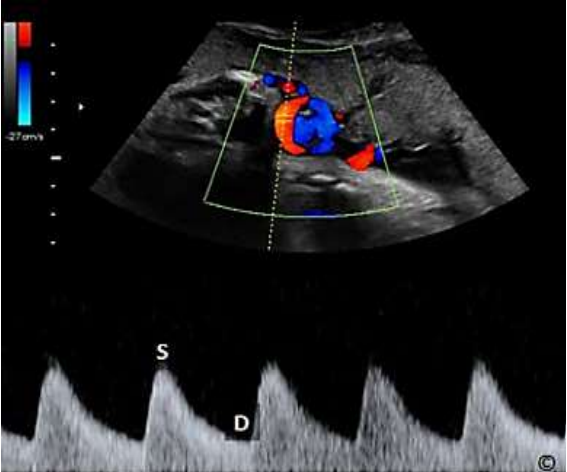

Assinale a alternativa que apresenta qual a estrutura representada na imagem a seguir.

Médico - Ultrassonografia em Obstetrícia